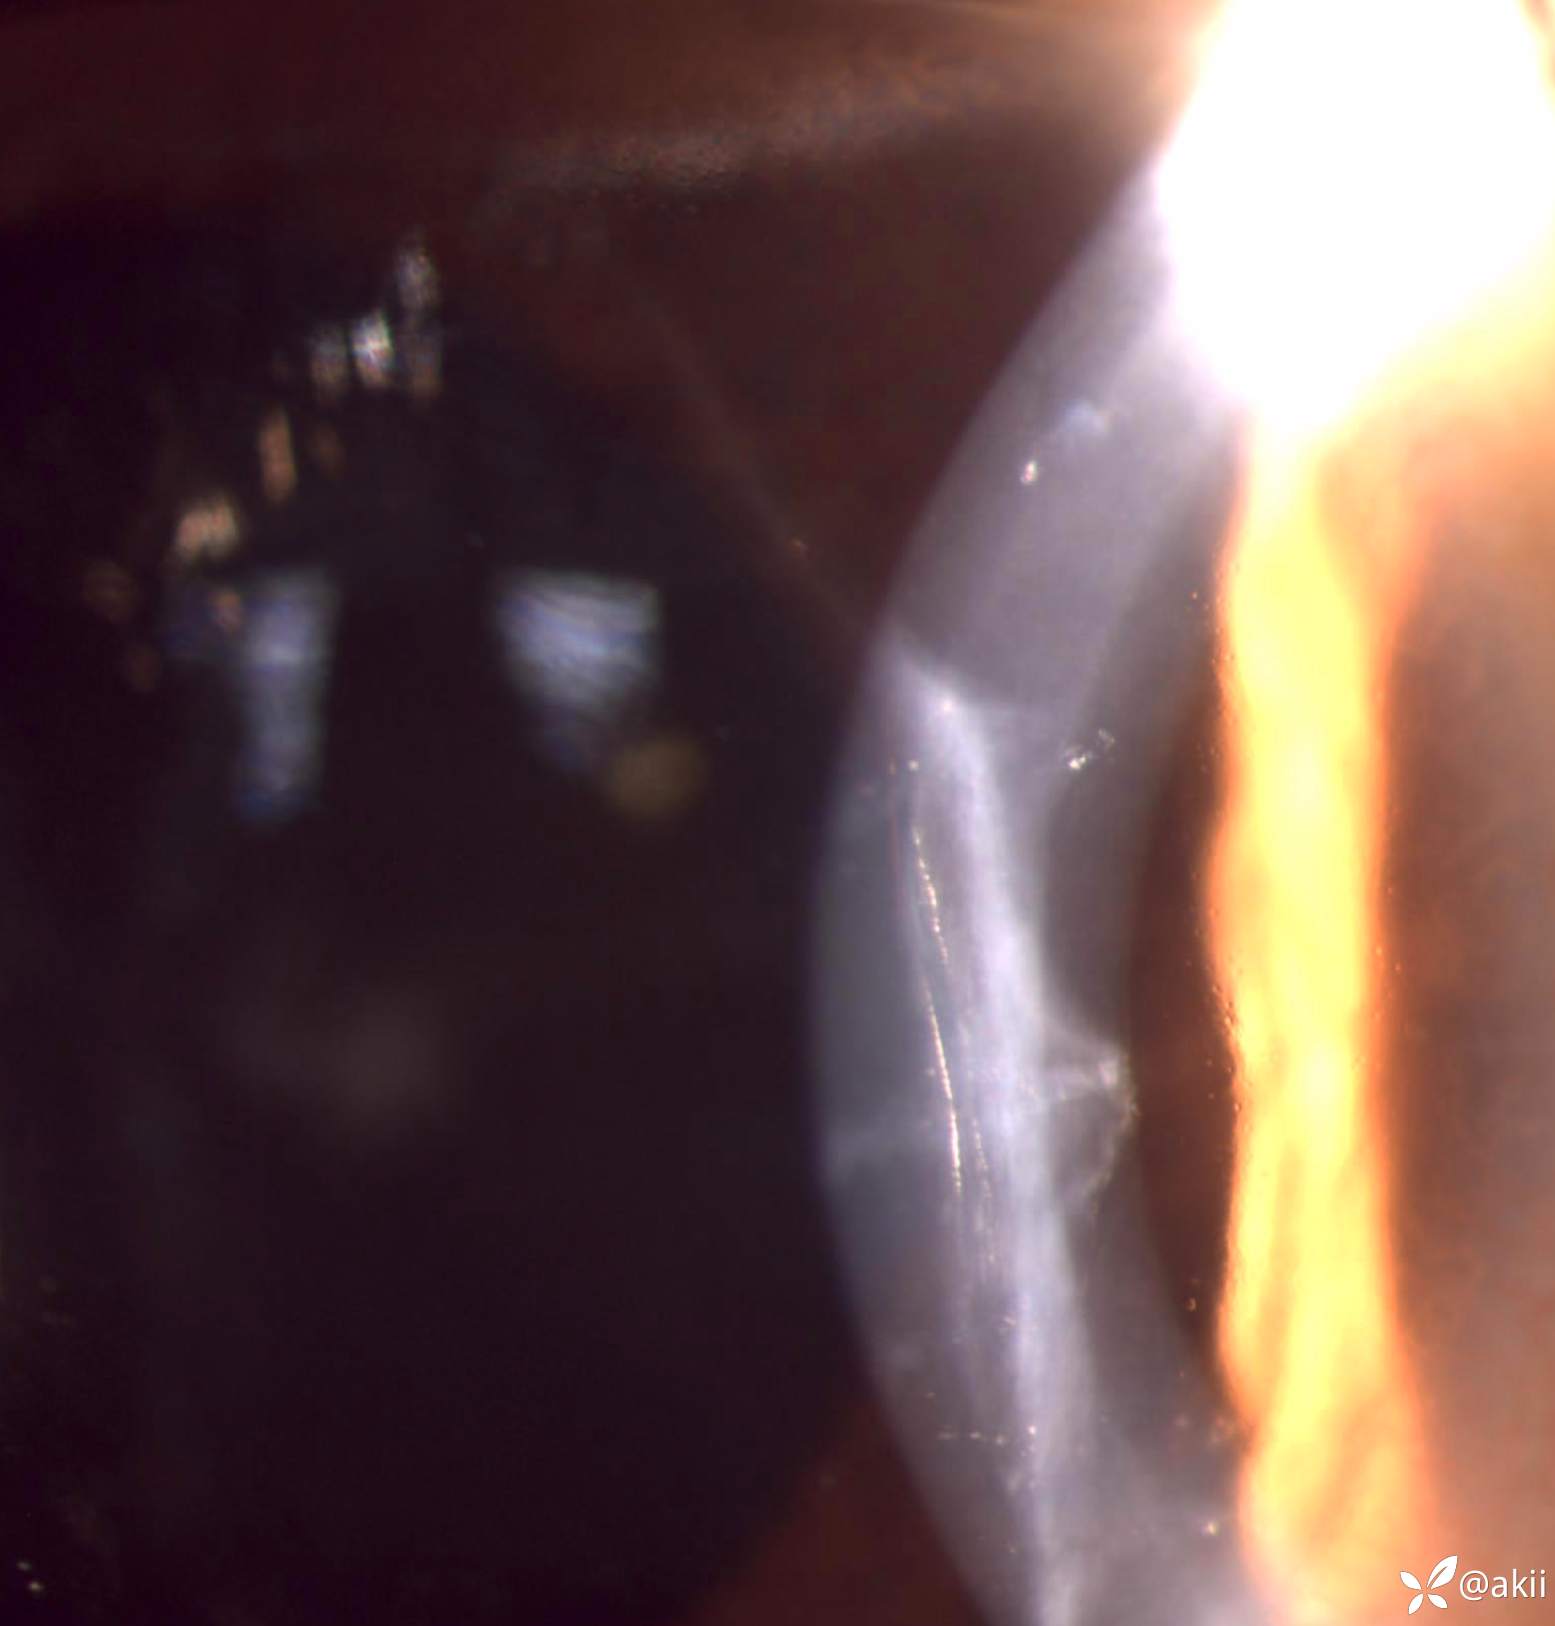

术前角膜陈旧性瘢痕

术后1天,缝线偏紧,前房小气泡

4-6点钟位松解切口